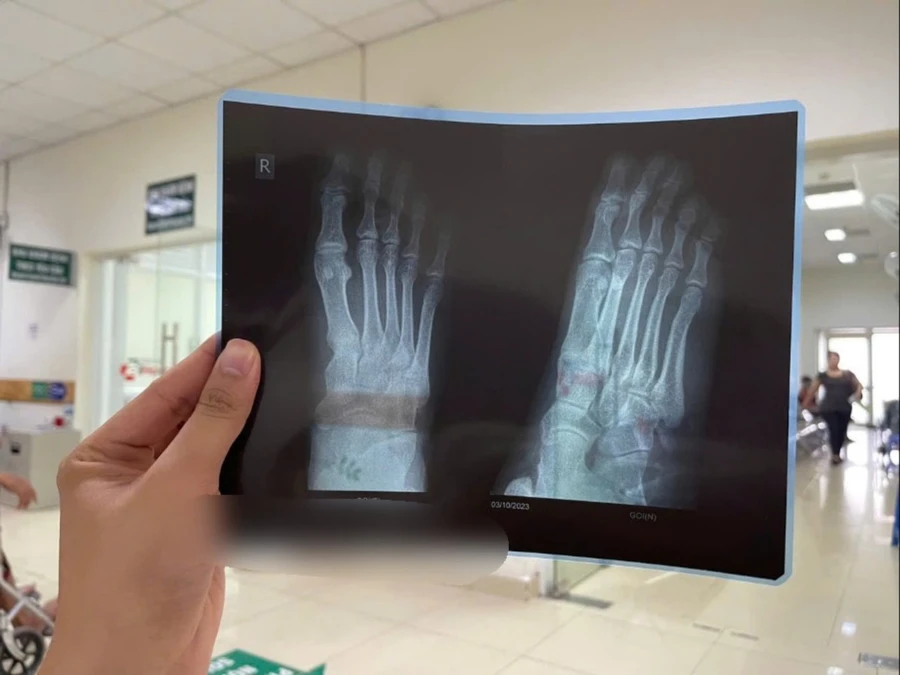

| Nhiều người lầm tưởng các cơn đau là do bệnh lý về xương khớp nhưng kết quả ghi nhận không có bất thường. |

Tuy nhiên, tình trạng không cải thiện, anh V. nghĩ mình bị chấn thương xương nên quyết định đến bệnh viện chụp X-quang. Kết quả chụp X-quang không ghi nhận bất thường ở chân, không có dấu hiệu tổn thương. Sau khi được chỉ định làm xét nghiệm, định lượng acid uric trong máu của anh V. là 612 micromol/l.